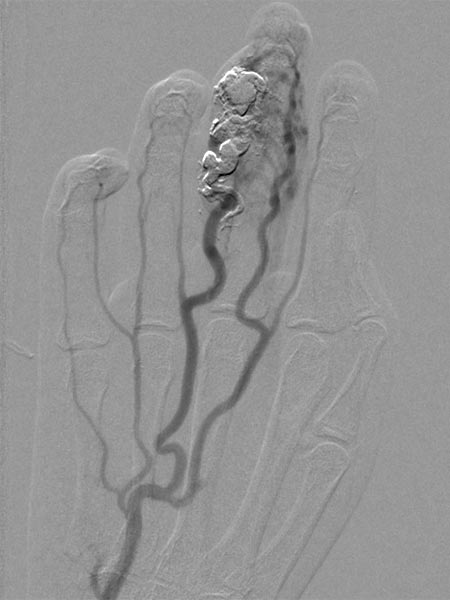

Das Rezidiv der AVM hier in der vergrößerten Zielaufnahme des D III während der Angiographie mit deutlicher Vergrößerung im Vergleich zu den alten Angiographien (nicht abgebildet). Die DSA-Aufnahmen nach transarterieller antegrader Punktion der Arteria brachialis zeigen eine hypervaskularisierte AVM von Fingermittel und -endglied.

Angiographische Abschlußkontrolle mittels Katheterangiographie der rechten Hand von transarteriell über die Arteria ulnaris. Komplette Devaskularisation des AVM Nidus, keine Fast-flow-Shunts mehr angiographisch abzugrenzen. Der Befund ist damit resektionsfähig.